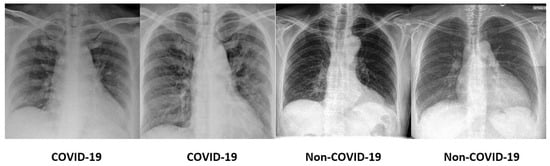

Random cropping produces synthetic images of smaller sizes ( r 5 , c 5 ) and ( r 10 , c 10 ) , where ( r , c ) is the original image size. The small distortions produce more COVID-19 samples while preserving the prominent region of the chest radiographs. The output of random cropping is homogeneous to images with different distances between the focal spot and patient surface in radiography examinations. Figure 6 illustrates the sample chest X-ray images before and after random cropping.

Figure 6. Sample chest X-ray images: (a) original, (b) random cropping ( r 5 , c 5 ) and (c) random cropping ( r 10 , c 10 ) .